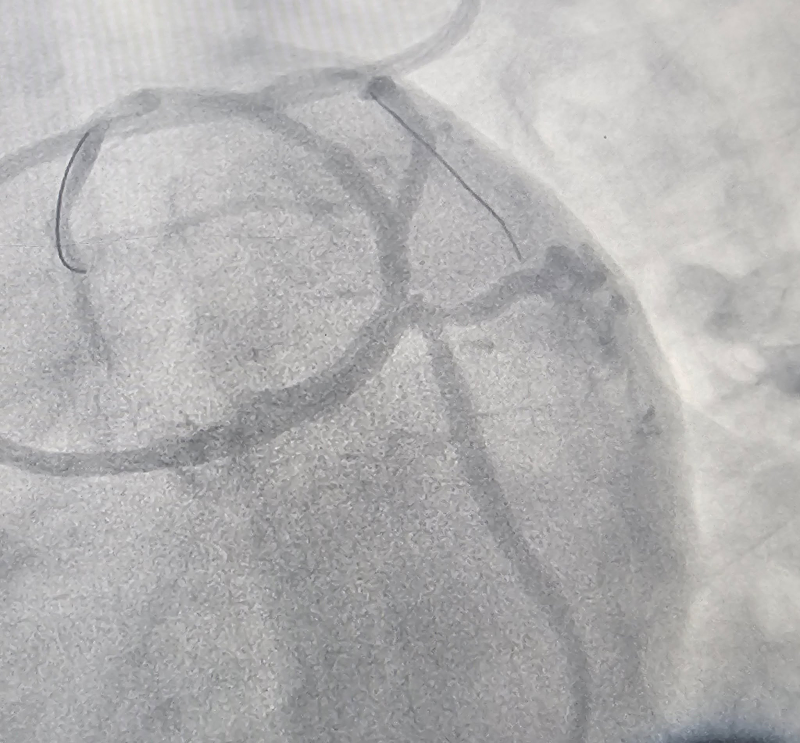

Các bác sĩ Khoa Tim mạch – Bệnh viện Bãi Cháy vừa can thiệp thành công cho bệnh nhân nam 34 tuổi bị nhồi máu cơ tim cấp. Kết quả chụp mạch vành cho thấy bệnh nhân hẹp 90% động mạch liên thất trước (LAD) và nhánh chéo 1 (Diag1). Người bệnh được xử trí kịp thời bằng kỹ thuật can thiệp đặt stent chỗ chia đôi (Mini-Crush), tái thông dòng chảy mạch vành, giúp bảo toàn chức năng tim.

Hình ảnh: trước và sau khi can thiệp